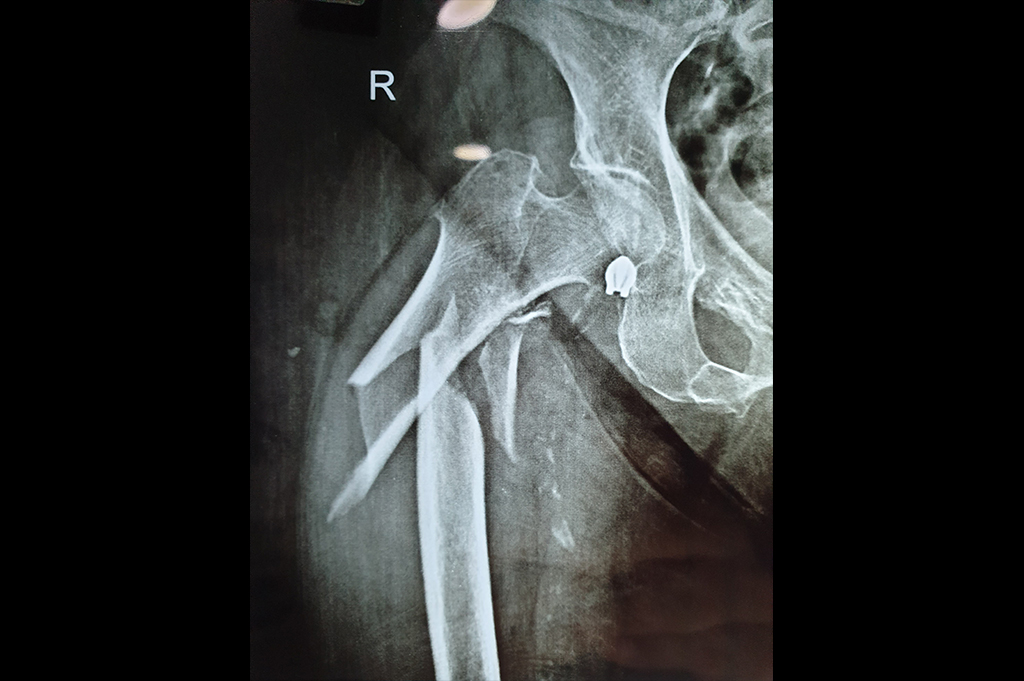

Neck Femur Fracture